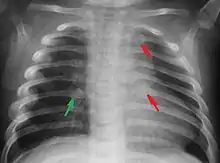

Abuzul fizic (denumit și violență fizică[3][4] ) constă în atingeri sau contacte fizice dureroase ne-accidentale, inclusiv în intimidarea fizică îndreptată asupra copilului (de exemplu gestul cuiva de a ridica mâna asupra unui copil). Abuzul fizic este reprezentat de acele traume fizice (care pot sa varieze în intensitate de la mici vânătăi la fracturi sau chiar moartea minorului) ca rezultat al înțepării, pălmuirii, lovirii, mușcării, scuturării, îmbrâncirii, aruncării, sufocării, lovirii (cu mâna, cu piciorul sau alt obiect contondent), arderii, legării, încătușării, sechestrării, cauzate de din partea persoanei abuzatoare; aceste traume sunt considerate abuz indiferent dacă persoana abuzatoare a intenționat să rănească copilul sau nu.[5] Fapta unei persoane adulte de a asista fără să intervină la aplicarea violenței sau de încuraja aplicarea violenței asupra copiilor pe care îi are în îngrijire, violență aplicată de către alți minori (ca de exemplu frații mai mari ce lovesc frații mai mici sau colegii mari din colectivitate ce lovesc pe colegii mai mici) este de asemenea considerată o formă de abuz fizic. Violența în familie este definită de Legea nr. 217/2003 (bibliografia) actualizată și se referă la violența îndreptată împotriva oricărui membru al familiei.